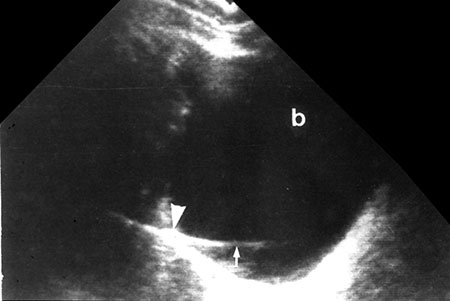

Hence echoes within the returning beam include from liquid as well as solid structure and averaged by the process or consequently the boundaries between solid tissues and fluid is seen as a low echogenic and indistinct structure. It can mimic sludge or layered material (concrements, blood clots) in the urinary bladder (Figs 1.19 and 1.20).

Fig. 1.19: Beam width artifact: The strong echoes from a pocket of gas in a pelvic gut loop (arrowhead) smear across the bladder (arrow)